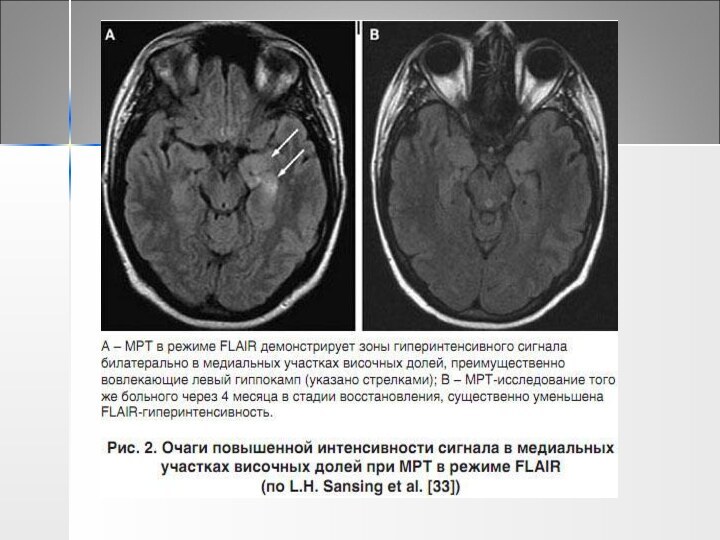

Слайд 43 МРТ головного мозга

50-90% паранеопластических неврологических синдромов на Т2-взвешанных

МРТ головного мозга50-90% паранеопластических неврологических синдромов на Т2-взвешанных изображениях и в

изображениях и в режиме FLAIR дают гиперинтенсивные очаги, расположенные

в поверхностном и глубоком сером и прилежащем белом веществе (очаги редко копят контраст).

При МРТ в динамике нарастают выраженные атрофические изменения

Слайд 50 ЦСЖ - лимфоцитарный плеоцитоз, повышение содержания белка

На ЭЭГ

ЦСЖ - лимфоцитарный плеоцитоз, повышение содержания белкаНа ЭЭГ эпилептическая активностьМРТ различается

эпилептическая активность

МРТ различается в зависимости от вида АТ, вызывающих

лимбический энцефалит Гиперинтенсивные очаги на Т2-взвешенных изображениях и в режиме FLAIR в медиальных областях височных долей при анти-LGI 1-ассоциированном энцефалите , в то же время очаги практически отсутствуют при анти-GABAR энцефалитах